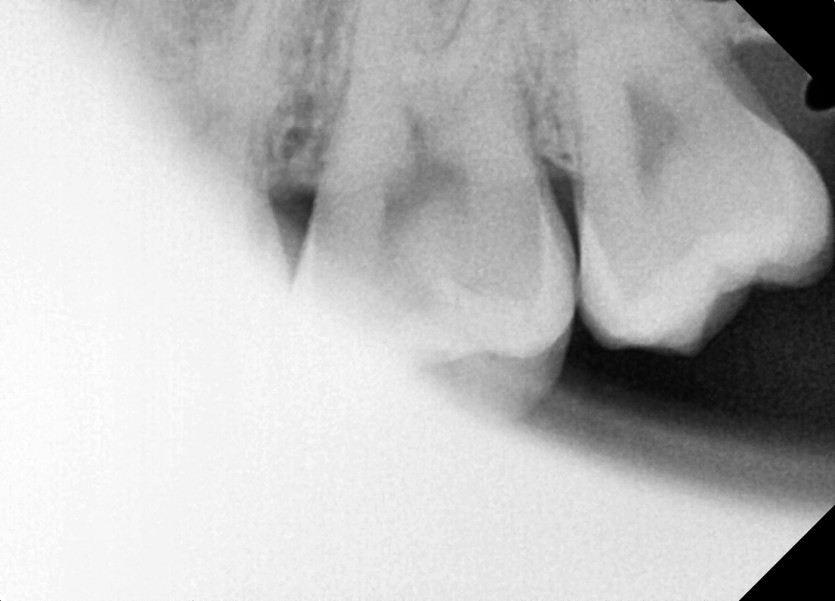

#28,38 사랑니 발치

구강 외과 전문의가 당일 발치했습니다.